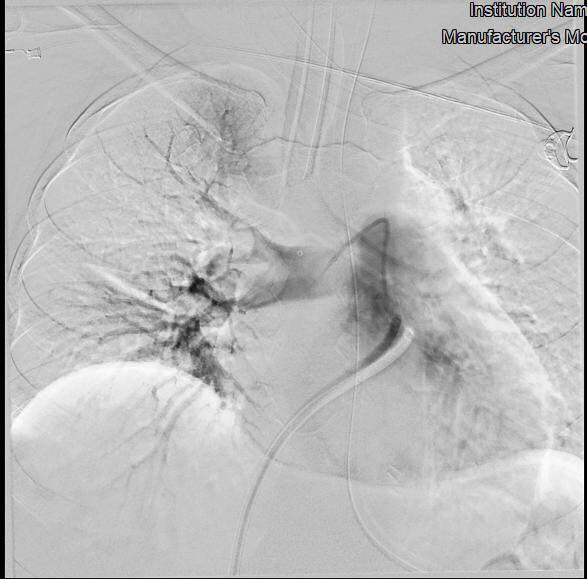

Bệnh nhân miền Tây may mắn 2 lần liên tục thoát khỏi cửa tử ảnh 1Hình chụp phổi bệnh nhân trước can thiệp.

Sau khi giải thích nguy cơ tử vong cao với người nhà, trên tinh thần “còn nước còn tát” các bác sĩ đã quyết định dùng phương pháp can thiệp nội mạch hút huyết khối. Sau đó các bác sĩ đã tiến hành can thiệp nội mạch cấp cứu sử dụng máy DSA, các ống thông được đưa từ tĩnh mạch đùi đến động mạch phổi và hút huyết khối tái thông lại động mạch phổi.

Sau hơn 1 giờ làm thủ thuật, ê-kip đã hút huyết khối thành công, tái thông được hoàn toàn động mạch phổi bị tắc, tình trạng hô hấp bệnh nhân được cải thiện nhanh chóng ngay sau thủ thuật.